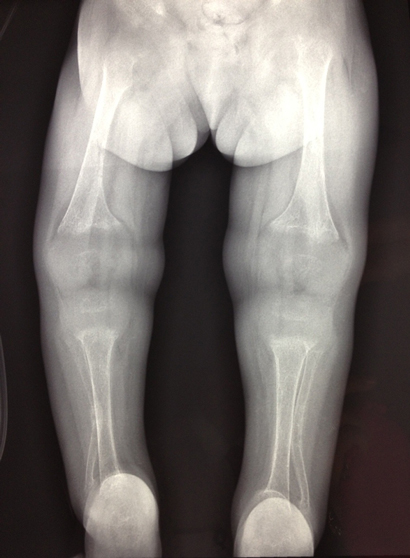

On examination, the patient was mildly dehydrated, listless, miserable and mildly tachypnoeic, with intercostal recession. Her anterior fontanelle was large. Rachitic rosary, tibial bowing and widened metaphyses of the wrists and knees were evident. No bruising of the skin was noted.

The patient had low serum total calcium and inorganic phosphate levels and a markedly elevated alkaline phosphatase level (Box 1). A skeletal survey showed significantly osteopenic bones, with flaring of the metaphyses in the long bones, soft tissue swelling around the elbow and wrist joints, and steep acetabular angles (Box 2). She had acute and healed fractures in multiple places: the right proximal ulnar shaft; both distal radial shafts; mid shafts of the second, third and fourth metacarpals of the right hand; mid shaft of the second metacarpal of the left hand; and mid shafts of the third metatarsals of both feet.

Sixteen months after discharge, at 3 years of age, the patient demonstrated good catch-up in weight (12.6 kg; 10–25th centile), with a growth velocity of 7.8 cm/year (25–50th centile). She was walking unaided and walking up and down stairs. Metaphyseal widening and tibial bowing had decreased but were still present on clinical examination. She continued to receive calcitriol at a dose of 0.07 µg/kg/day, and her PTH, calcium and phosphate levels were within reference intervals (Box 1). A renal ultrasound produced normal results, with no evidence of nephrocalcinosis.